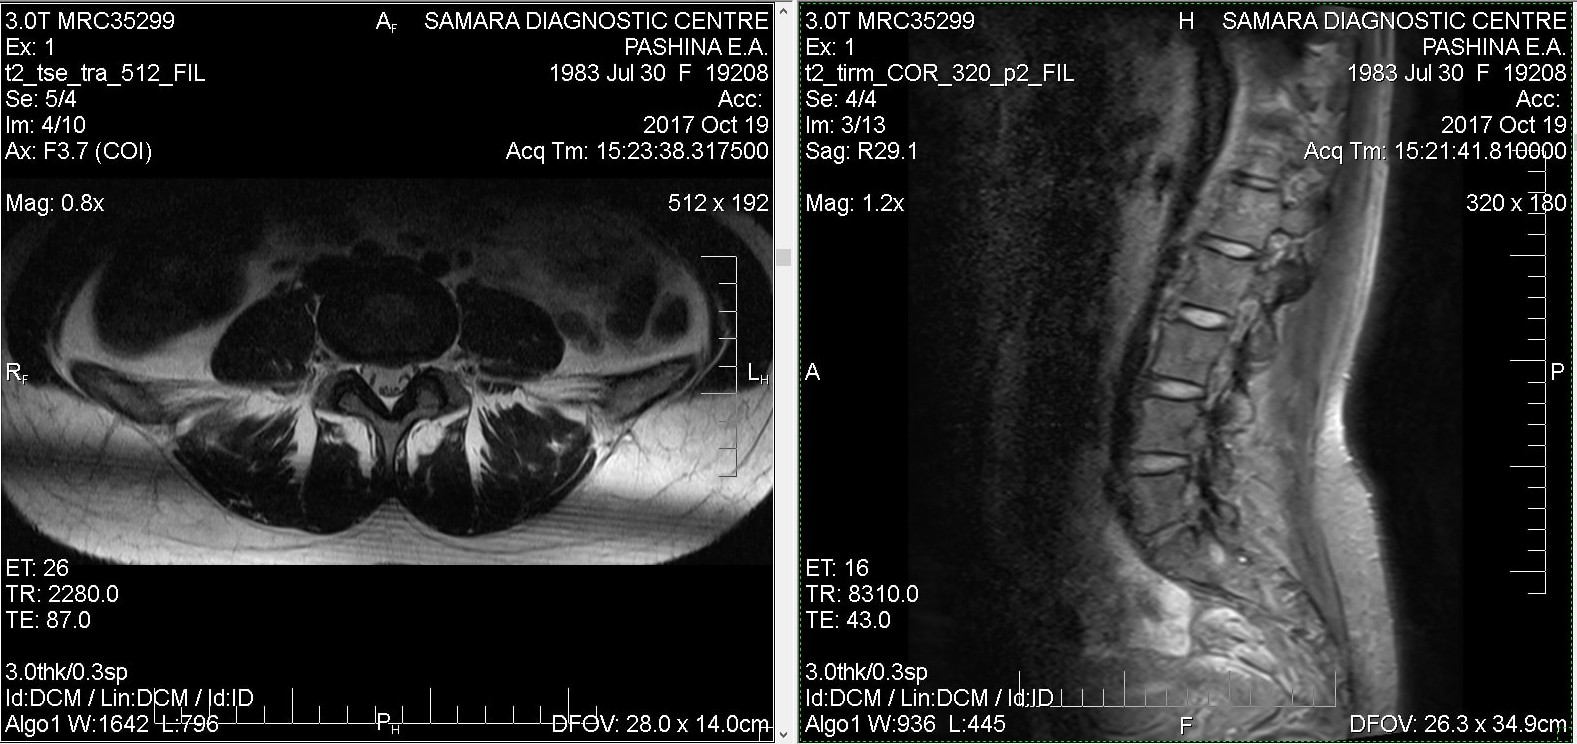

Тренировки с межпозвоночной грыжей.